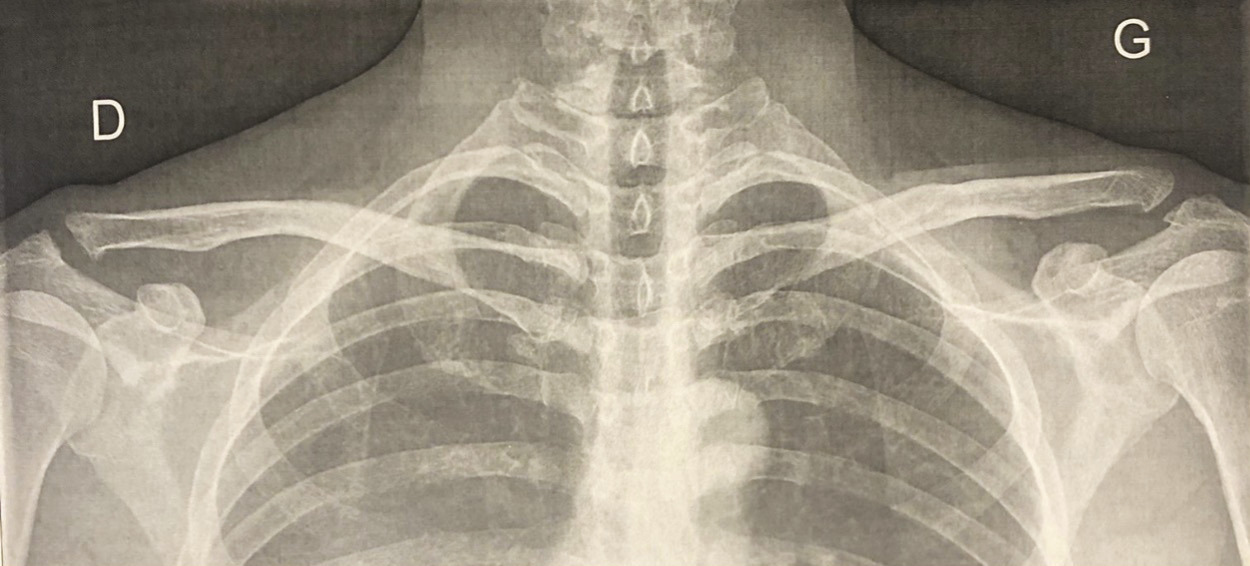

Une radiographie comparative centrée sur les articulations acromioclaviculaires est l’examen de première intention en cas de suspicion clinique d’OPTCD (fig. 2). Elle révèle une résorption de l’os sous-chondral de l’extrémité distale de la clavicule, plus rarement de l’acromion. Dans les formes évoluées, il est possible d’observer une véritable ostéolyse de plusieurs centimètres responsable d’un élargissement de l’interligne.

Cependant, du fait d’un retard d’apparition des lésions, jusqu’à 50 % de patients atteints d’OPTCD ont une radiographie normale au stade initial. L’IRM étant plus sensible au stade précoce, elle doit compléter une radiographie normale. Elle peut permettre d’objectiver une fracture sous-chondrale, pathognomonique, et des signes indirects d’atteinte tels qu’un épanchement acromioclaviculaire ou une tuméfaction des parties molles.5